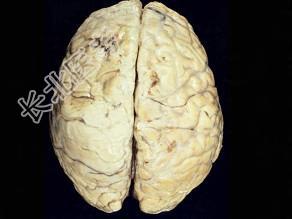

单项选择题观察图片所示病理,流脑脑膜炎期的病变特点下列说法正确的为 ( )

A、早期能发生脑室孔阻塞

B、病变主要部位在软脑膜及蛛网膜

C、脑实质无炎症

D、颅底部炎症粘连可导致脑神经损害

E、硬脑膜水肿